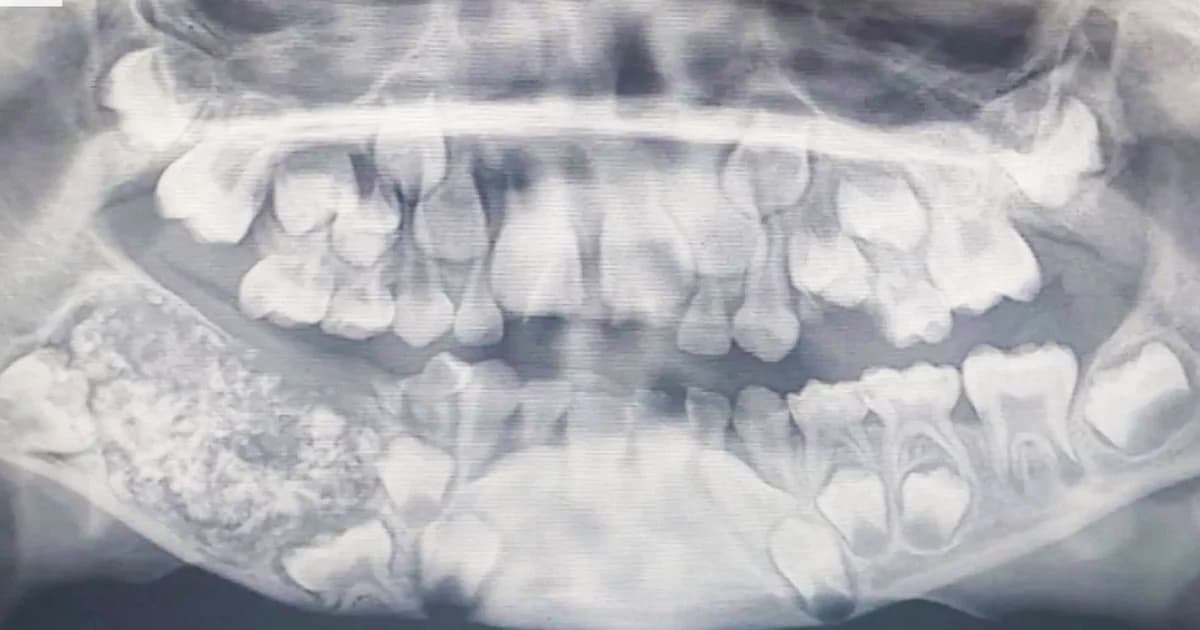

วันที่ 2 ส.ค. 2562 สำนักข่าวต่างประเทศรายงานว่า เด็กชายชาวอินเดีย วัย 7 ขวบ ถูกนำตัวเข้ารักษาที่โรงพยาบาลในเมืองเจนไน ประเทศอินเดีย เมื่อเดือนกรกฎาคมที่ผ่านมา หลังจากมีอาการหน้าบวมและปวดฟันกราม เมื่อหมอตรวจด้วยการสแกน และ Xray ก็พบเนื้อเยื่อคล้ายถุงฝังอยู่ในกรามล่างเต็มไปด้วยฟันที่ผิดปกติจำนวนมาก ก่อนจะตัดสินใจผ่าตัดนำถุงออกจากปากของเด็กได้สำเร็จ และ พบฟันทั้งหมด 526 ซี่ มีหลากหลายขนาด หลังทันตแพทย์ทำการผ่าตัดถอนฟันเสร็จสิ้น เด็กชายชาวอินเดียรับอนุญาตให้ออกจากโรงพยาบาลใน 3 วัน โดยไม่พบอาการแทรกซ้อนแต่อย่างใด

เบื้องต้นทีมแพทย์ระบุว่า น่าจะเป็นเคสแรกในโลกที่ผู้ป่วยมีฟันซี่เล็กซี่น้อยมากมายขนาดนี้ โดยเด็กชายชาวอินเดีย วัย 7 ขวบ มีกรามบวมในช่วง 4 ปีที่ผ่านมา แต่ไม่ได้รับการรักษา เนื่องจากไม่ยอมให้ความร่วมมือในการตรวจอาการ เป็นโรคหายากที่เรียกว่า “โรครากฟันงอก” โดยสาเหตุของความผิดปกตินี้ยังไม่ทราบแน่ชัดว่าเกิดจากอะไร แต่สันนิษฐานว่าน่าจะเกิดจากความผิดปกติของยีน หรือ ไม่ ก็อาจสืบเนื่องจากปัจจัยแวดล้อมต่างๆ อย่างเช่น ได้รับสารกัมมันตรังสี ซึ่งขณะนี้มีความเป็นไปได้ที่ เด็กจะมีฟันงอกเกินปกติไปอีกระยะหนึ่ง